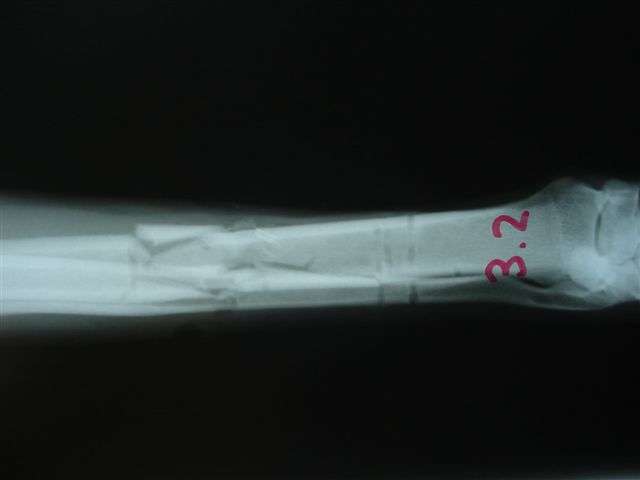

Fijación Externa

Casos prácticos alumnos.